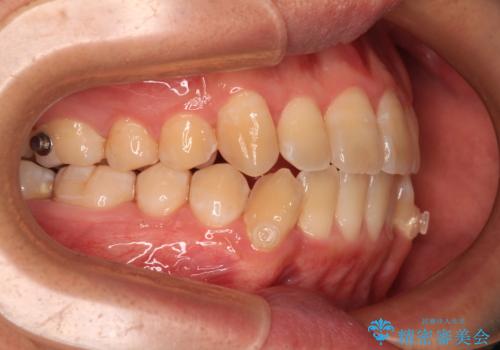

- インビザライン

オープンバイトは舌の突出癖により誘発され、治療後も突出癖が残っている容易に後戻りしてしまいます。

治療期間を短縮するためにも、舌突出癖の改善が極めて重要となります。

特にインビザラインではIPRという歯と歯の間を削る処置を多用するため、後戻りによりスペースが生じやすくなるため、治療初期段階での舌のトレーニングが必須となります。